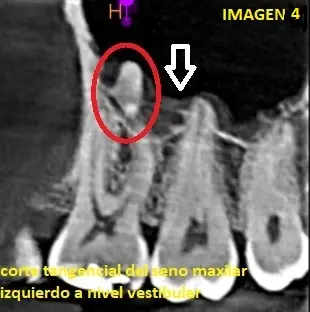

En el corte tangencial del seno maxilar izquierdo, hacia nivel vestibular, podemos observar la calcificacion sobre la raiz de la pieza dentaria 26 (circulo) y un leve engrosamiento de la membrana sinusal del seno (flecha blanca) (ver imagen 4)